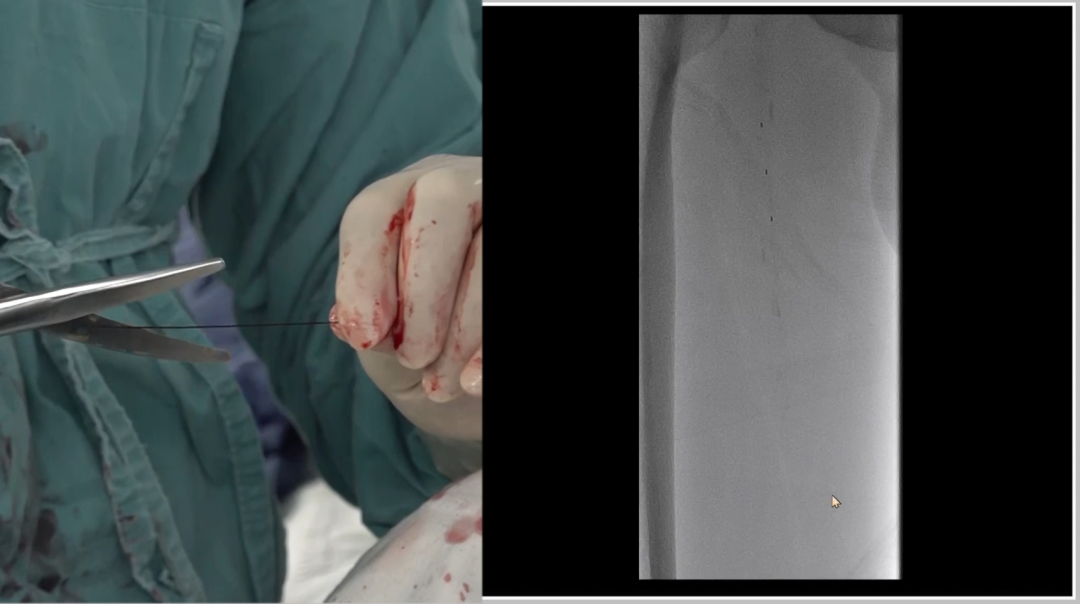

管腔准备与支架植入

预扩张:使用球囊扩张病变段,造影提示长段限流性夹层,需支架覆盖

治疗模式:因股腘动脉直径<4.5mm,选择DCB(药物涂层球囊)+BMS(裸金属支架)联合方案;

支架选择:在DCB扩张导管进行管腔准备后,植入2枚5mm INNOVA支架,其优势在于尾端定位精准,尤其适合累及开口或分叉的病变。

手术结果:

血流通畅,解剖与功能双重改善

最终造影显示:支架定位准确、形态良好,股浅动脉、腘动脉及膝下动脉显影清晰,血流通畅。